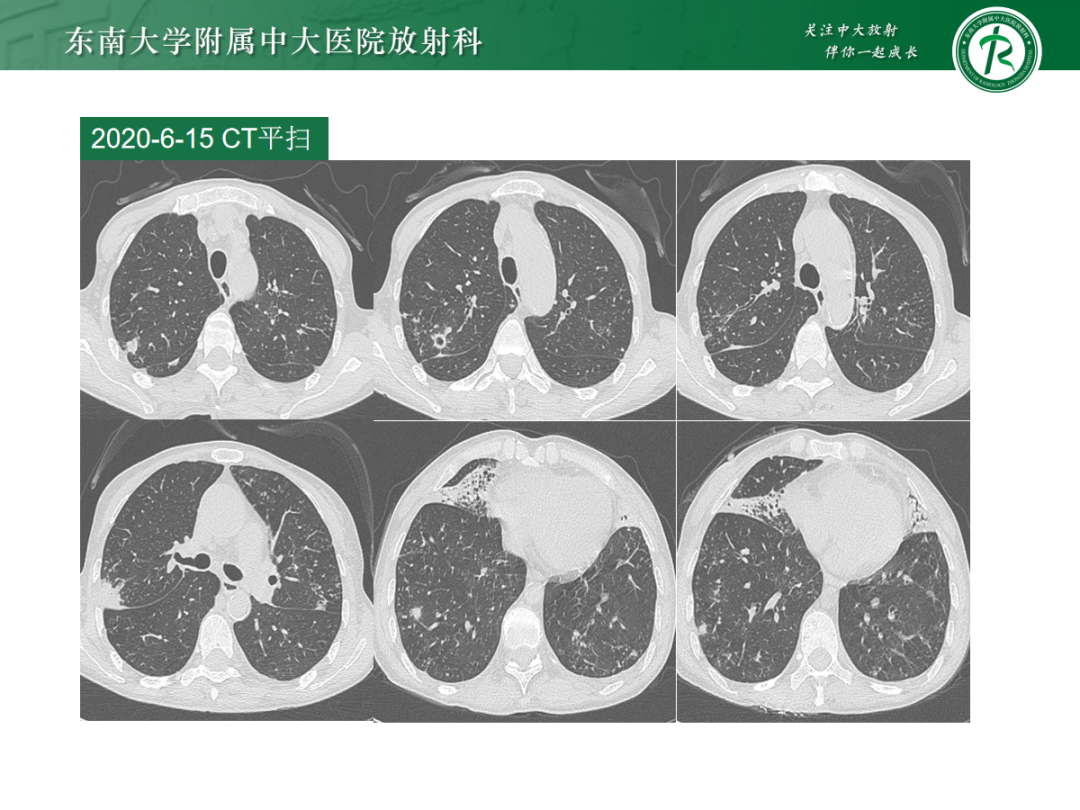

• 病例1:鸟型分枝杆菌复合体肺病

• 病例2:肺诺卡菌病

• 病例3:肺结核

• 病例4:气道侵袭性肺曲霉菌病

影像诊断思路